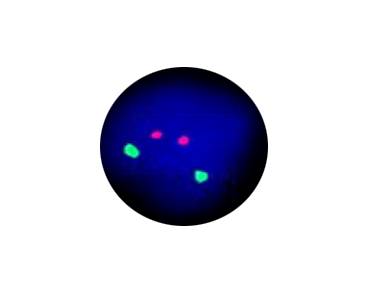

5q Segment Deletion

Probe Description: EGR1 /CSF1R

Cat.No.: CF1127